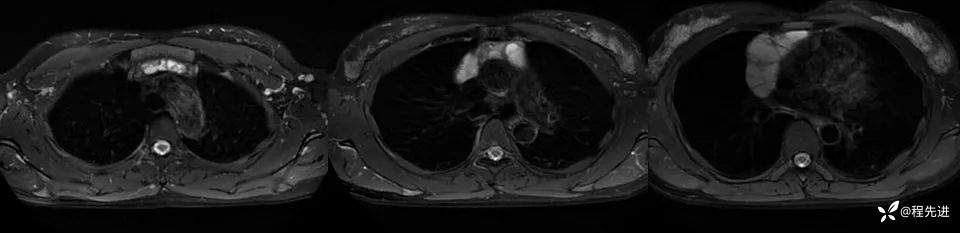

MR

T2抑脂